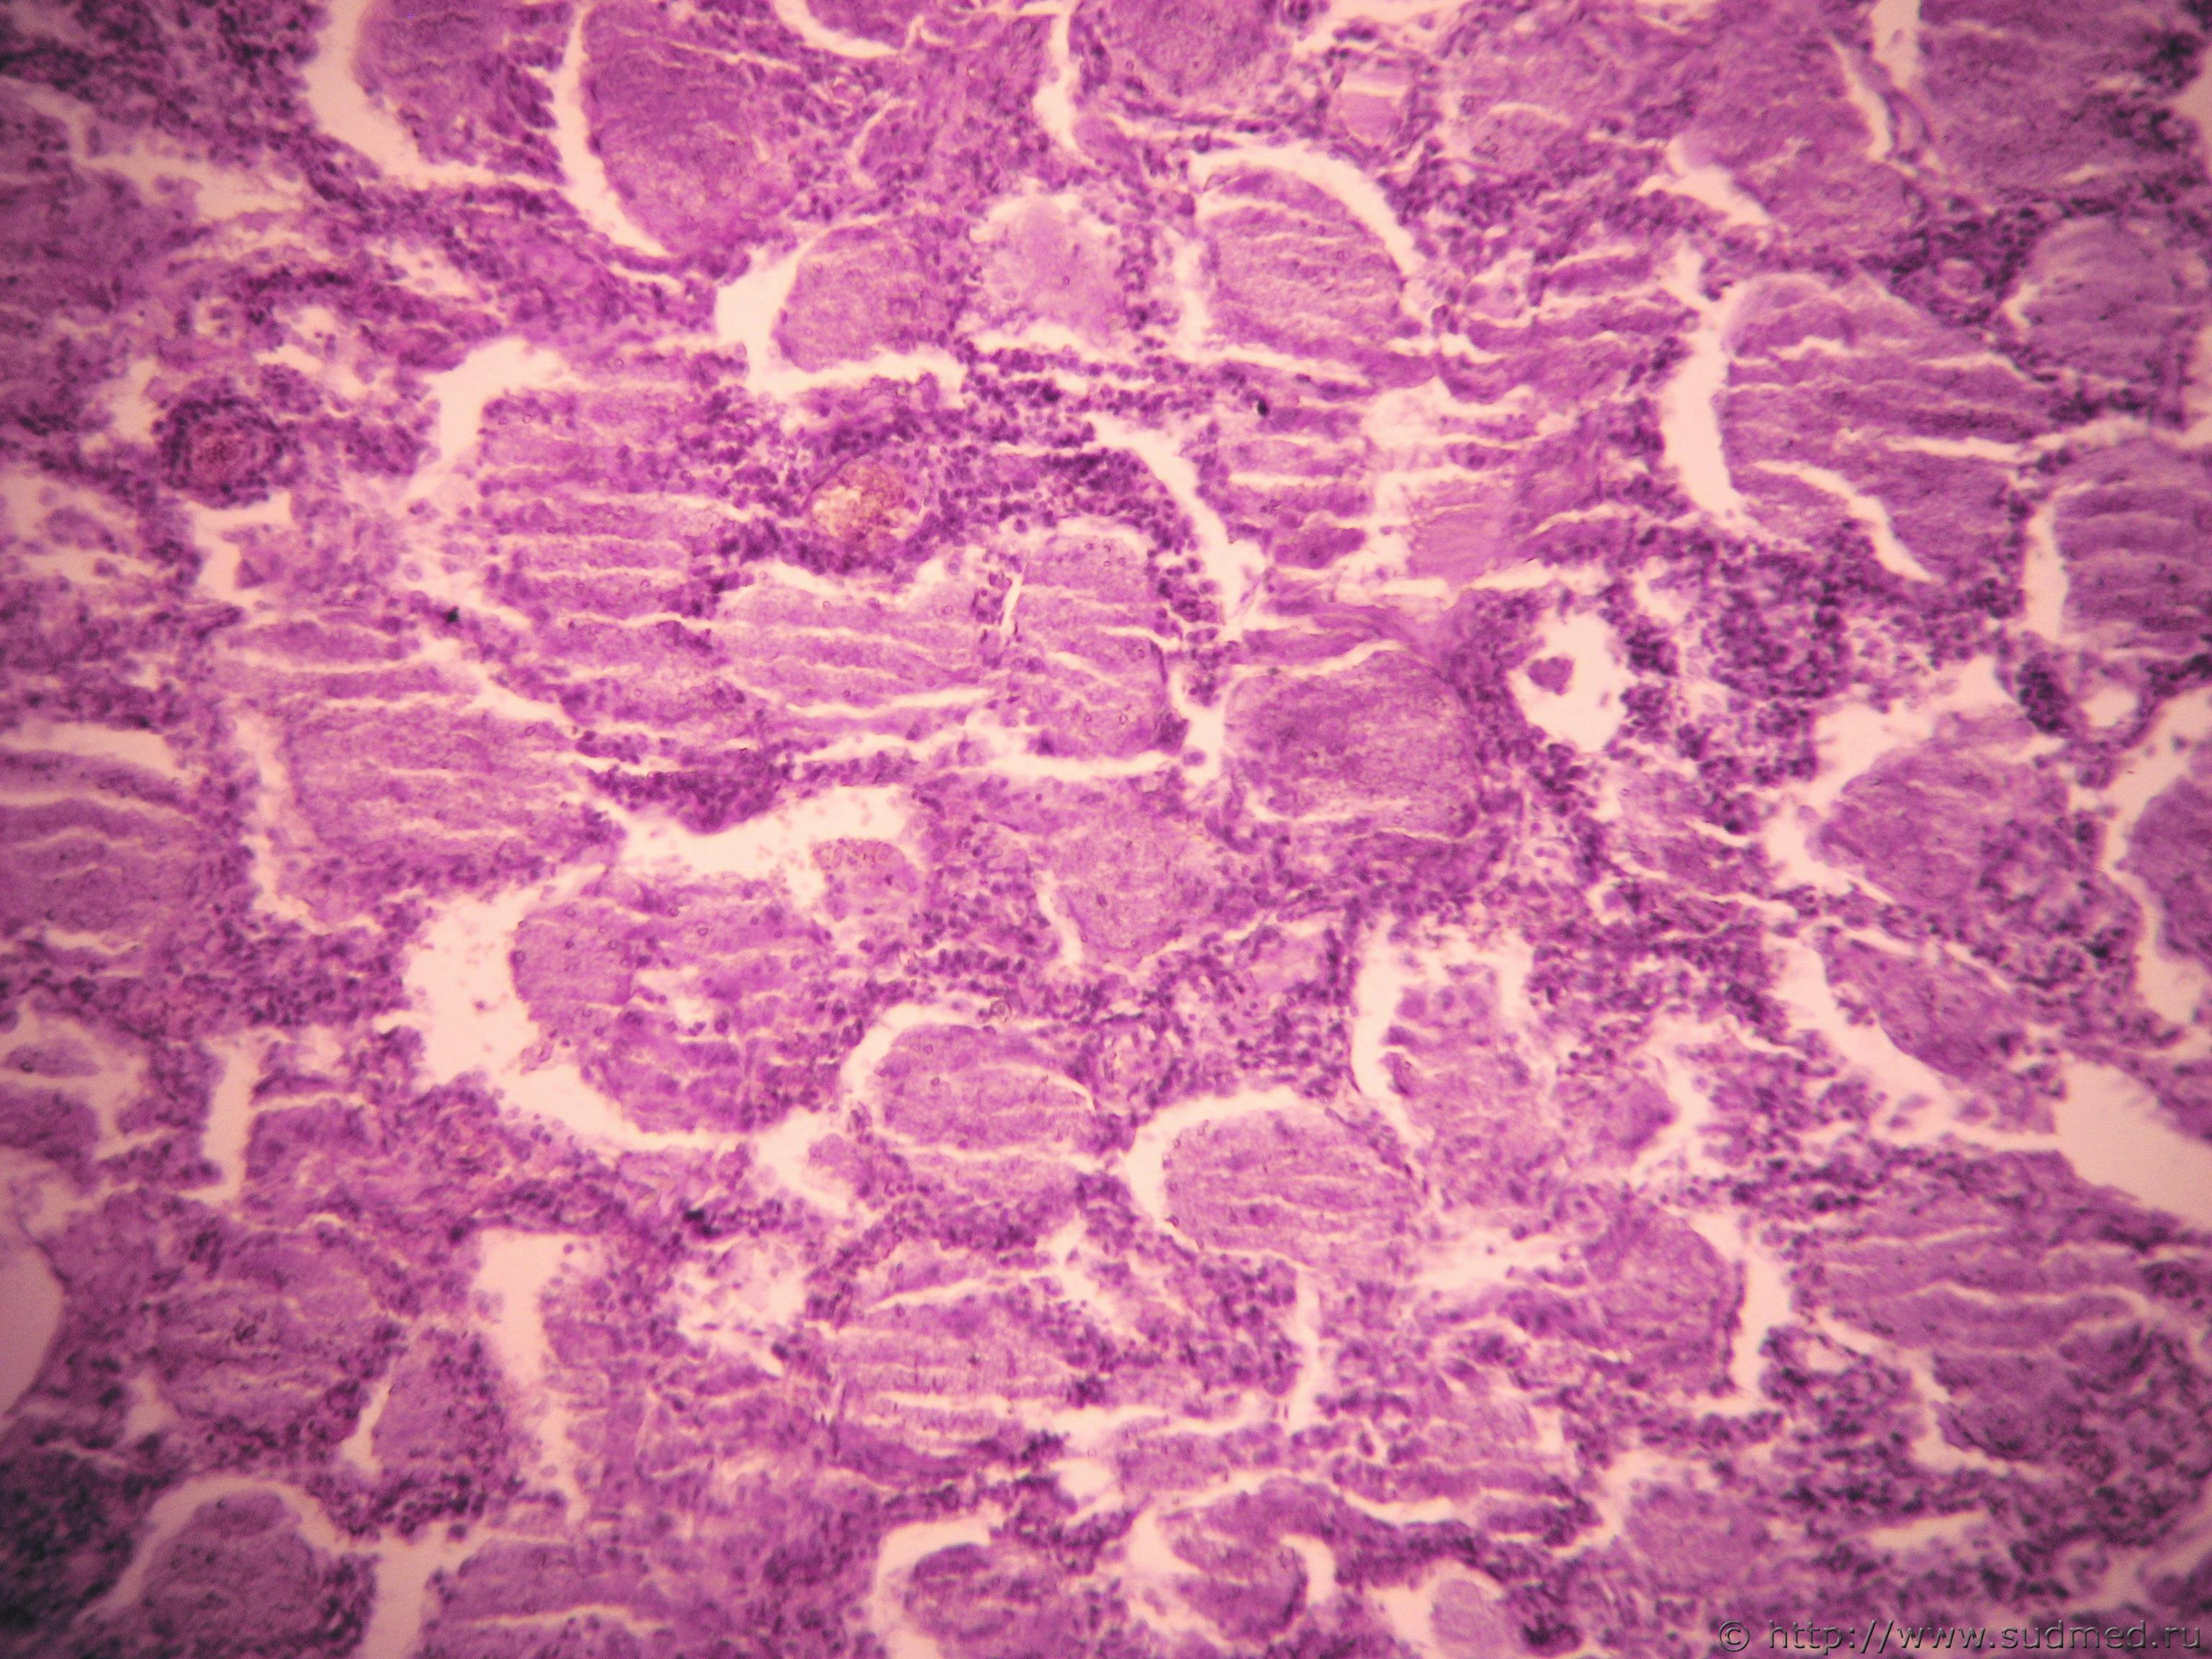

Вторые две: пневмоцистная пневмония, ГЭ, по Grocott не красим